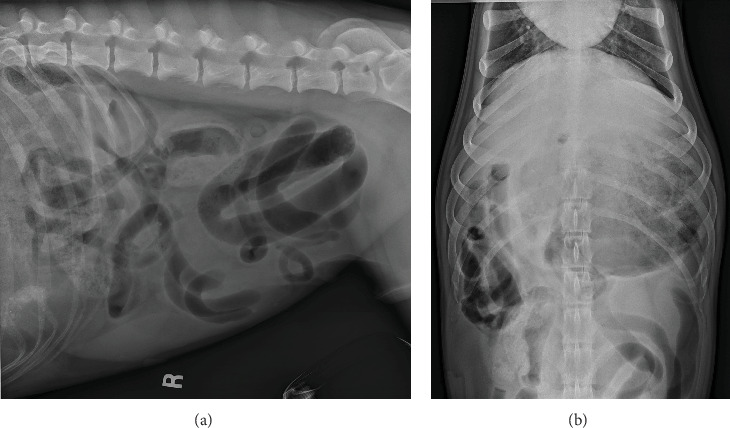

A 6-year-old, male neutered, German Shorthaired Pointer was evaluated for acute onset of emesis, tenesmus, and restlessness. Abdominal radiographs suggested gastrointestinal obstruction or torsion. An exploratory laparotomy revealed an omental-to-mesenteric adhesion causing entrapment and strangulation of a segment of the jejunum, along with several other adhesions. The patient had undergone two previous laparotomies, which likely contributed to the extensive adhesion formation found intraoperatively. While postsurgical adhesion formation is a known complication in both human and veterinary medicine, this case is notable for the unusual origin of the adhesions arising from the omentum. Furthermore, the severity of strangulation resulting from this adhesion required more extensive surgery and posed a higher risk for long-term gastrointestinal complications, such as short bowel syndrome.